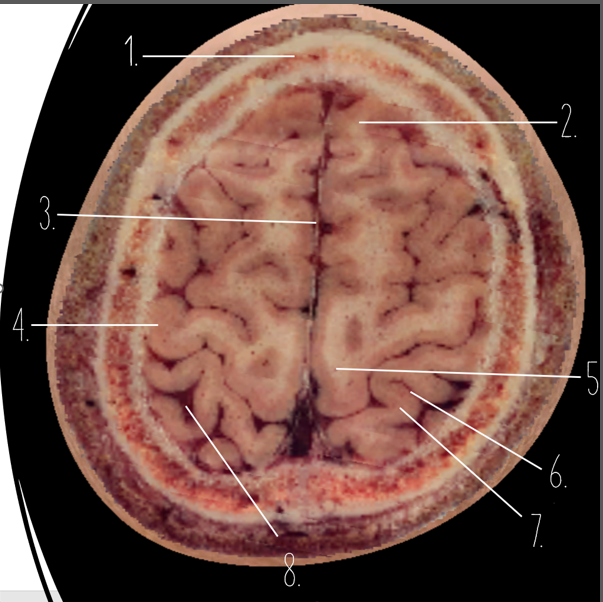

1

Frontal Bone

2

Frontal Lobe

3?

Falx Cerebri

4?

Gray Matter

5?

White Matter

6?

Sulcus

7?

Gyrus

8?

Fissure